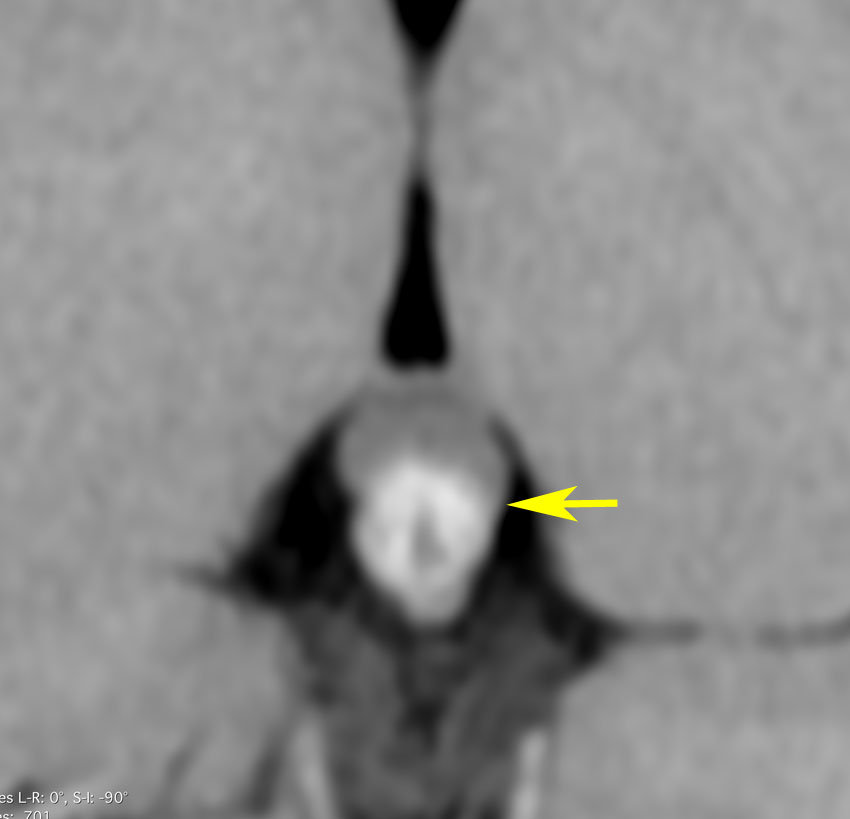

放射線が外れやすい部位は再発源となります

側脳室先端(前角,後角,側頭角,閂),下垂体と大脳基底核に放射線が入らないとその部位から再発します。

再発ジャーミノーマの画像です。延髄背側の閂 ovexという部位に再発しています。

このパターンはとても多いです。なぜかというと,全脳室照射の時に,第4脳室下端のovexの上衣 ependyum を照射野に入れない放射線治療医の先生がいるからです。放射線科の先生にもちょっとした知識が必要なのです。

これは再治療で腫瘍が消えても不可逆的な重症の延髄障害を残してしまいます。